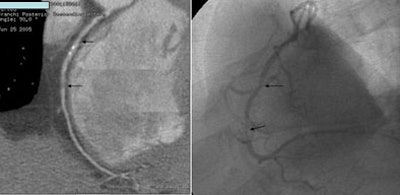

![]() |

| Coronary artery bypass grafts visualized on 64-slice CTA scan. All images courtesy of Dr. David Dowe. |